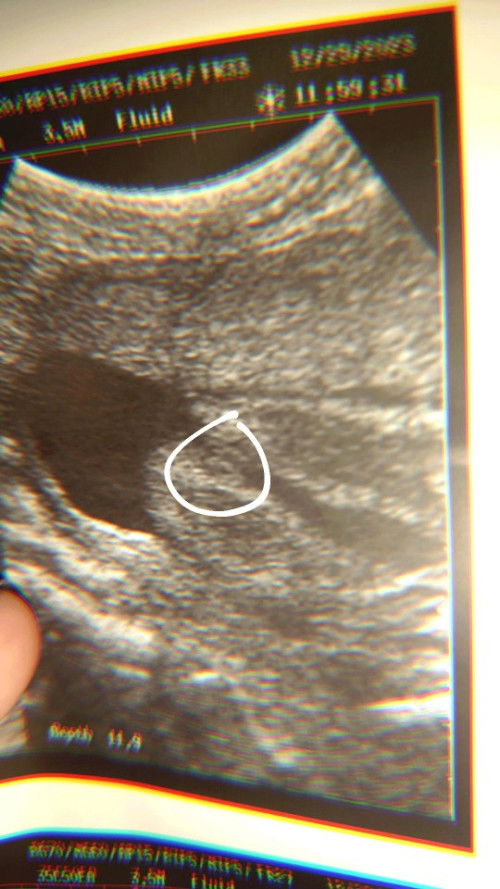

Hulaan ang gender 🤣🤣 Hindi pa sure eh pauulit ko pag 8mos para daw accurate

hamburger kaya Girl hihi 🤭😇

it's a girl for me. ☺️